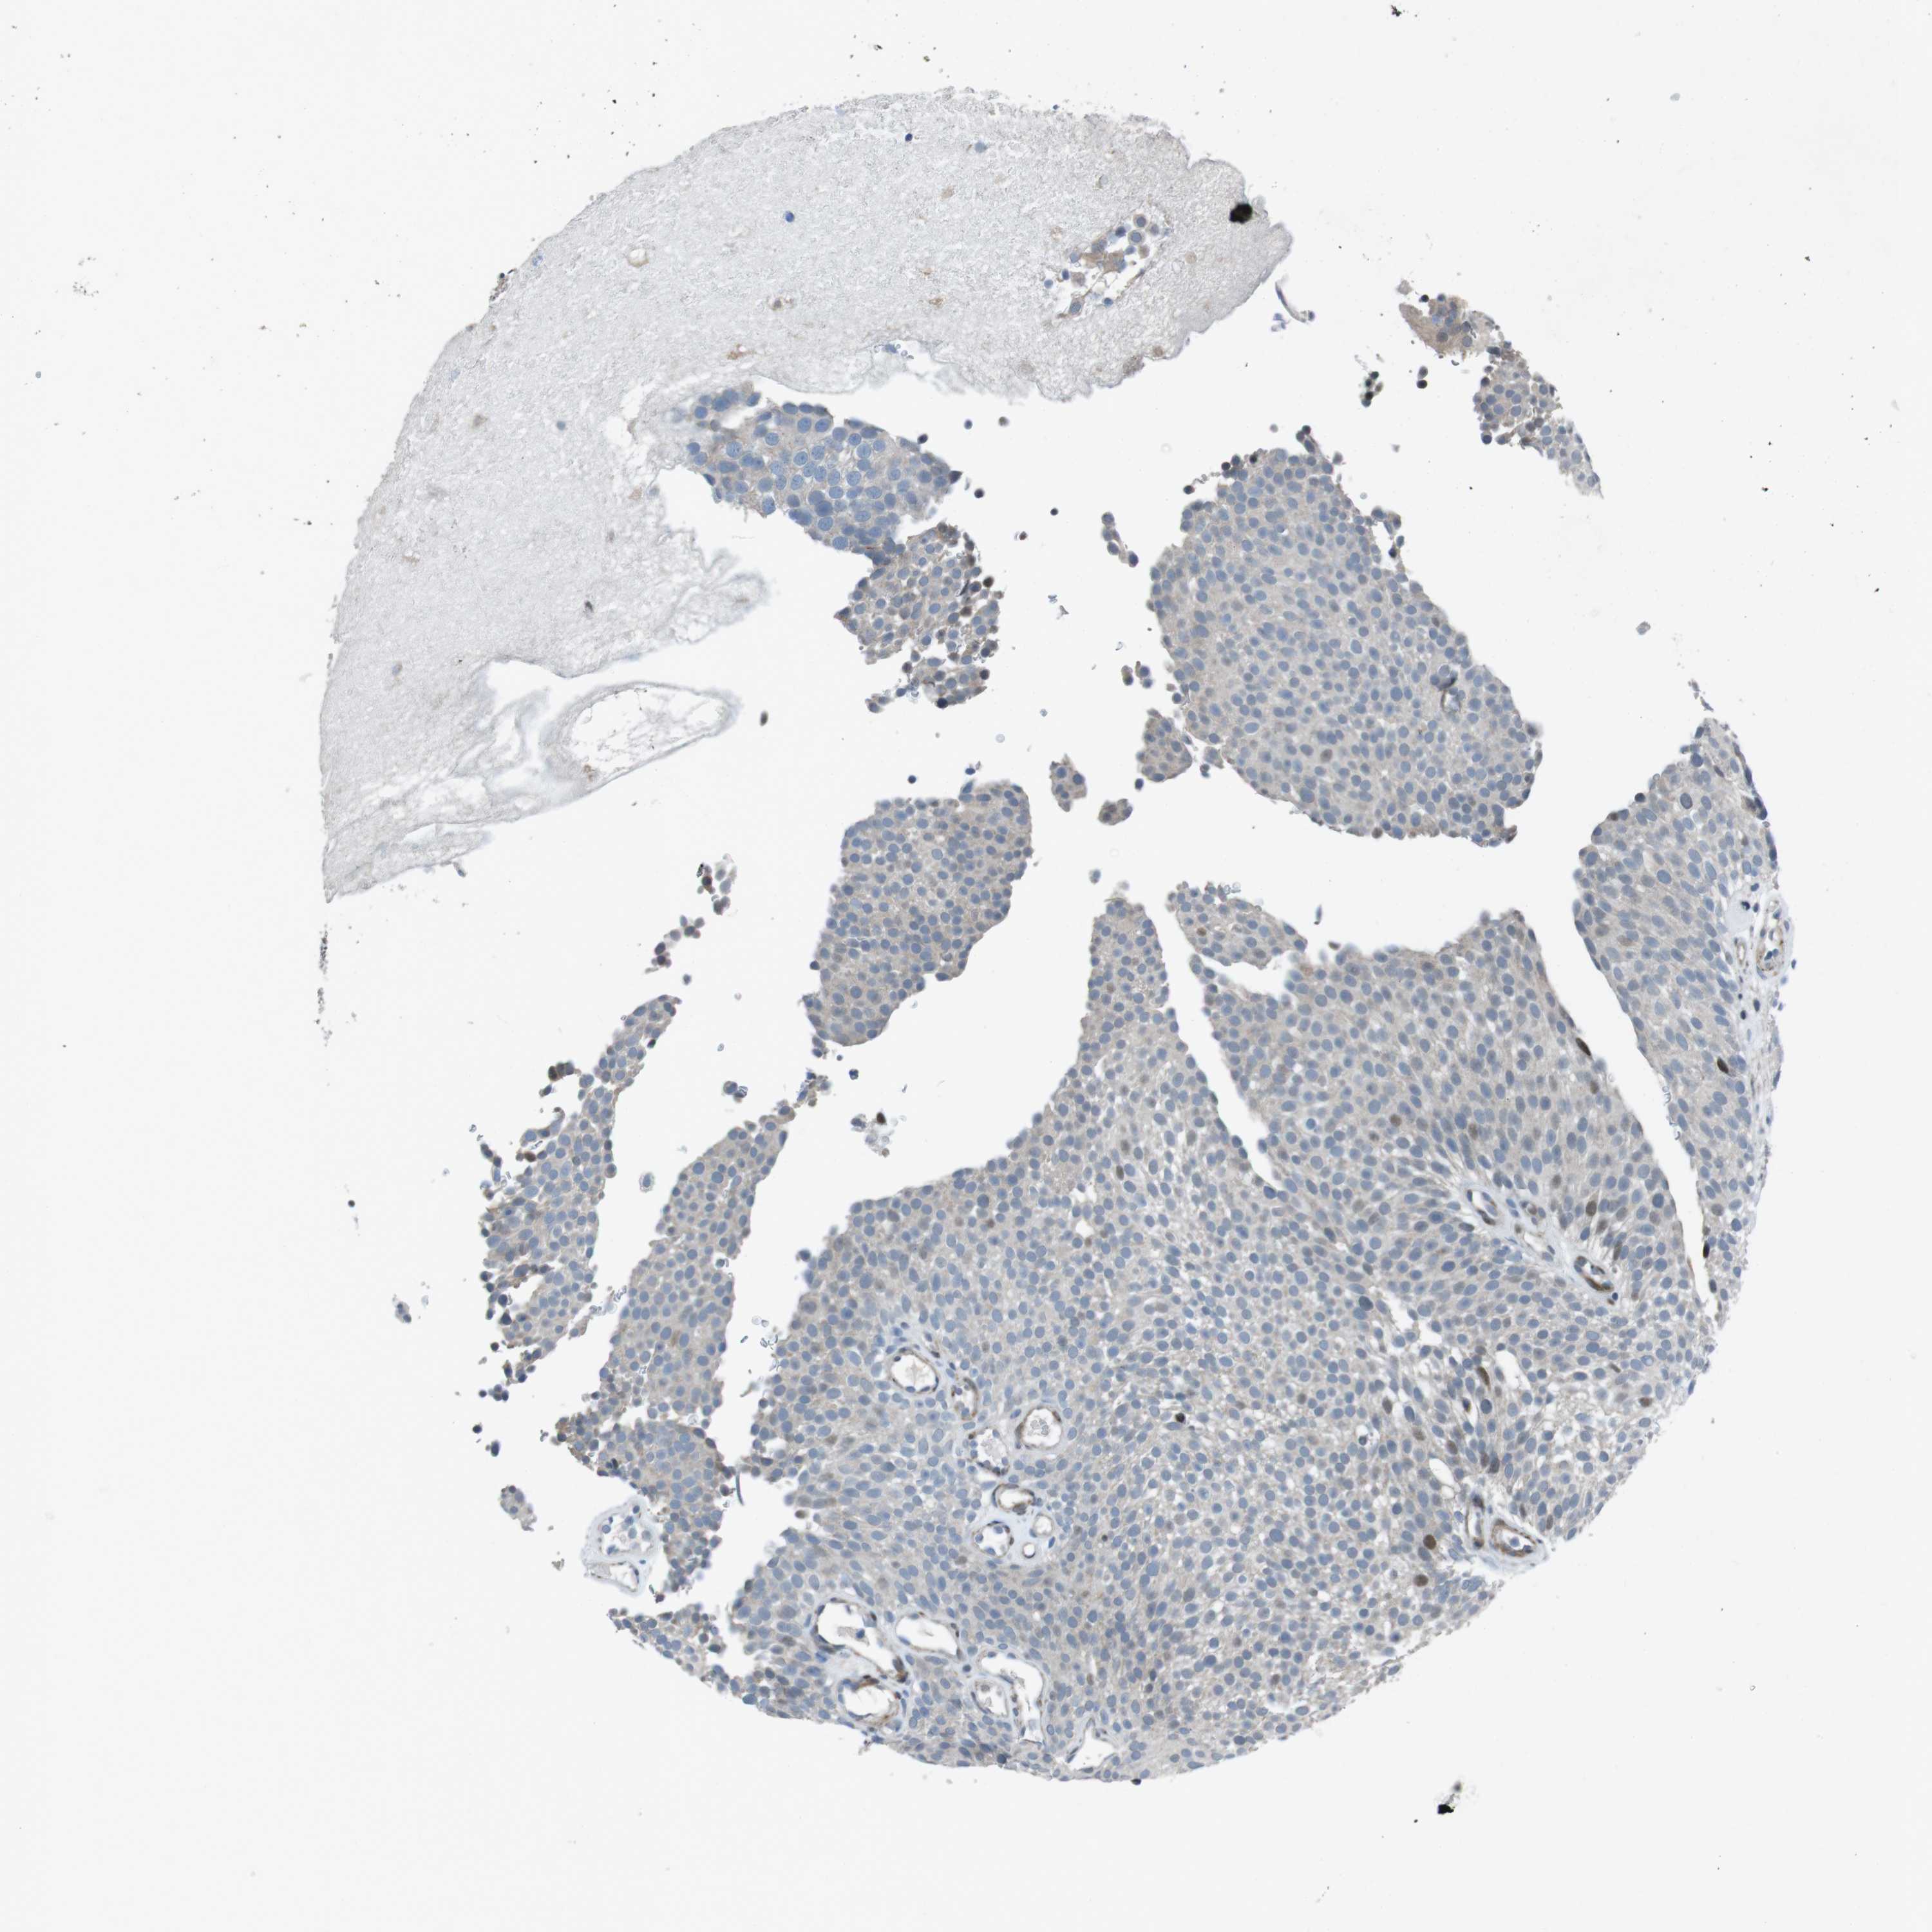

UROTHELIAL CANCER - Protein expressioni

A mouse-over function shows sample information and annotation data. Click on an image to view it in a full screen mode. Samples can be filtered based on level of antibody staining by selecting one or several of the following categories: high, medium, low and not detected. The assay and annotation is described here.

Note that samples used for immunohistochemistry by the Human Protein Atlas do not correspond to samples in the TCGA dataset.

Antibody stainingi

Antibody staining in the annotated cell types in the current human tissue is reported as not detected, low, medium, or high, based on conventional immunohistochemistry profiling in selected tissues. This score is based on the combination of the staining intensity and fraction of stained cells.

Each image is clickable and will lead to virtual microscopy that enables deeper exploration of all samples and also displays staining intensity scores, fraction scores and subcellular localization as well as patient and tissue information for each sample.

Antibody HPA015629

Staining

High

Medium

Low

Not detected

Intensity

Strong

Moderate

Weak

Negative

Quantity

>75%

75%-25%

<25%

None

Location

Nuclear

Cytoplasmic/membranous

Cytoplasmic/membranous,nuclear

Urothelial carcinoma, Low grade